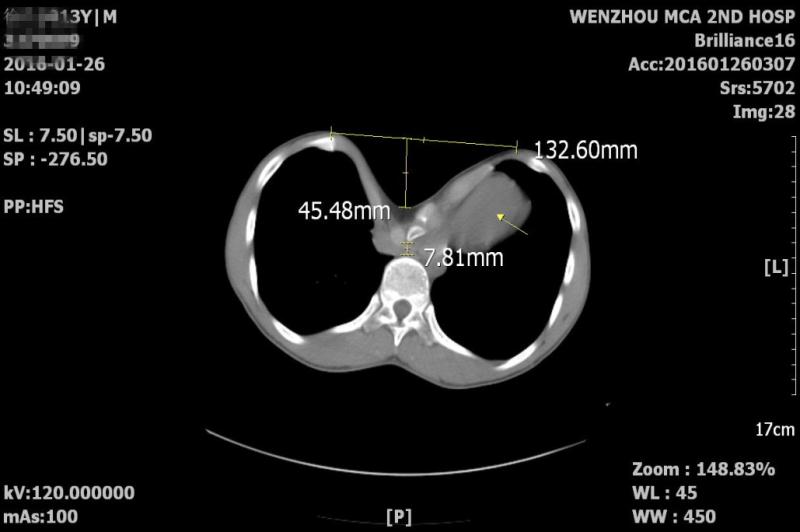

经医生检查,发现其胸骨中下部凹陷十分明显,形似漏斗。胸部CT提示前后胸壁间最短距离仅留下约一个小拇指厚度的空间,心脏完全被挤压至左侧胸腔,变形严重,也导致小康这半年来稍有剧烈活动,就透不过气或容易疲劳。这是典型的先天性漏斗胸,据了解,该病发病率约为0.1%,但是如此严重的患者在浙南地区、全省乃至全国都极为罕见。

先天性漏斗胸患者目前的手术方法是需要在前后胸壁间植入钢板撑起胸骨,但由于小康的情况较为特殊,留给医生操作的空间十分有限,又加上心脏紧贴胸骨,手术操作时极易伤及心脏,这也成为摆在医生面前的一道难题。我院心胸外科胡型锑主任和赵琦峰主任对小康的病情进行了全面细致的评估和分析,在充分考虑手术难度及危险因素的基础上,决定在常规两侧胸开切口外,再在最凹陷处再增加一个切口,而这个切口是给术者用手牵拉胸板留出空隙,再用手慢慢引导钢板穿过空隙所用,这对术者的经验和手法的要求非常之高。手术由胡型锑主任主刀,平时只用30-40分钟完成的手术,这次大概用了近一个小时的时间完成。术后小康气促情况明显好转,再经过一段时间的修整,小康就可以和其他孩子一样,享受运动带来的乐趣了。